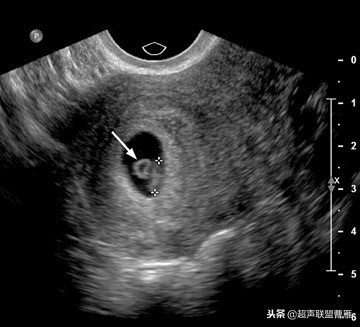

妊娠37天超声检查卵黄囊可以显示,羊膜腔及胚胎不能显示

真实的卵黄囊、胚体及羊膜腔形象

妊娠37天出现卵黄囊

在妊娠妊娠38天前后(36-40)天可以见到卵黄囊。 孕囊在6-9mm的可以见到其中有卵黄囊。